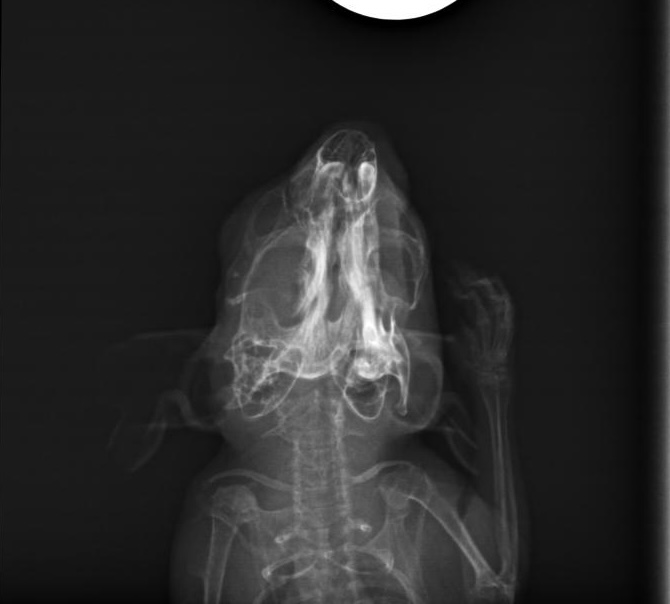

Also bin ich mit ihr am 15. Oktober zum Tierarzt gefahren und habe sie dort zusammen mit Freundin Leni abgegeben. Mit der Bitte die Zähne wirklich gut zu checken und auch ein Röntgenbild anzufertigen.

Mittags dann der Anruf: Klein Ida hat sich den Kiefer gebrochen. Mist, mist, mist! Tja nun... was ist hier die beste Lösung. Die Tierärztin und ich schweigen erst einmal... wägen ab. Doch wir sind uns einig, dass die kleine Maus eine Chance bekommen soll. Somit werden nur die vorderen Schneidezähne etwas gekürzt, da diese schon etwas zu lang waren und ansonsten bleibt uns nur die Versorgung mit Schmerzmittel und Brei.

Hier die Bilder, ich habe extra gefragt, ich darf sie teilen. Ich sehe darauf nix, aber ihr vielleicht ;)

ida-rb1.jpg

ida-rb2.jpg